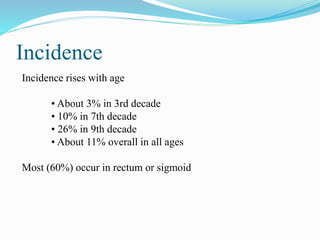

This document discusses colorectal polyps. It defines polyps and describes their types, including neoplastic and non-neoplastic polyps. It discusses adenomatous polyps in depth, noting their malignant potential increases with size over 1cm and villous architecture. Radiological diagnostic methods for polyps including single and double contrast barium enema and CT colonography are explained. The document provides an overview of polyp pathogenesis and genetic syndromes like FAP that increase cancer risk.